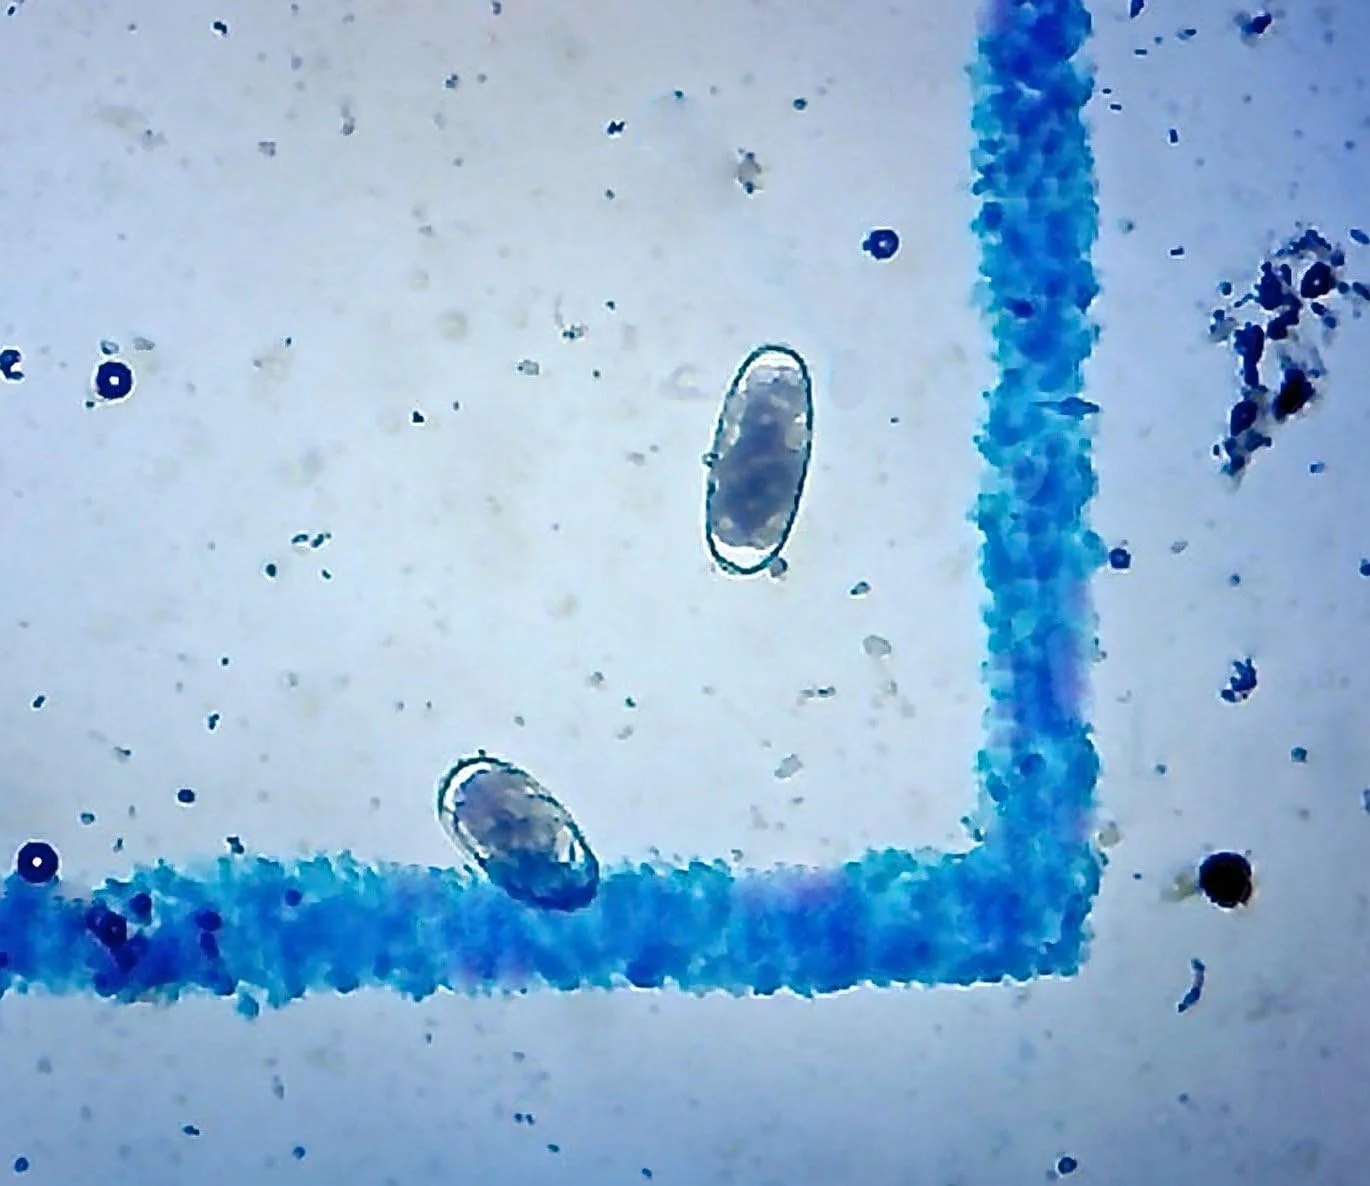

اسلاید میکروسکوپ متد مک مستر، اسلاید دو محفظه ای شمارش تخم انگل برای آزمایش و مدیریت انگل، شمارش تخم انگل در اسب ها، گوسفندها، بزها، تمیز کردن آسان، شبکه شفاف

اسلاید متد مک مستر برای انجام شمارش تخم انگل مدفوع استفاده می شود.